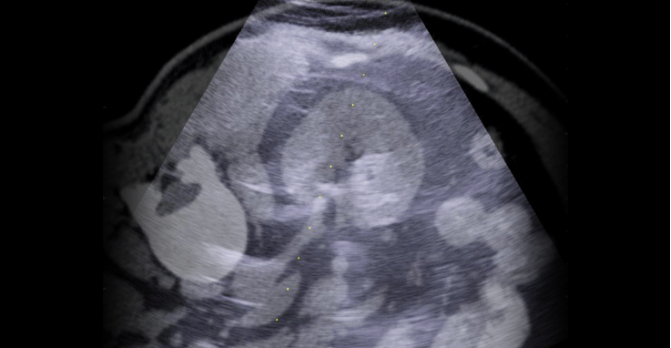

超声与CT/MRI影像实时融合

更清晰直观展现人体解剖结构

以超声为基础的影像融合

无CT、DSA等X光辐射